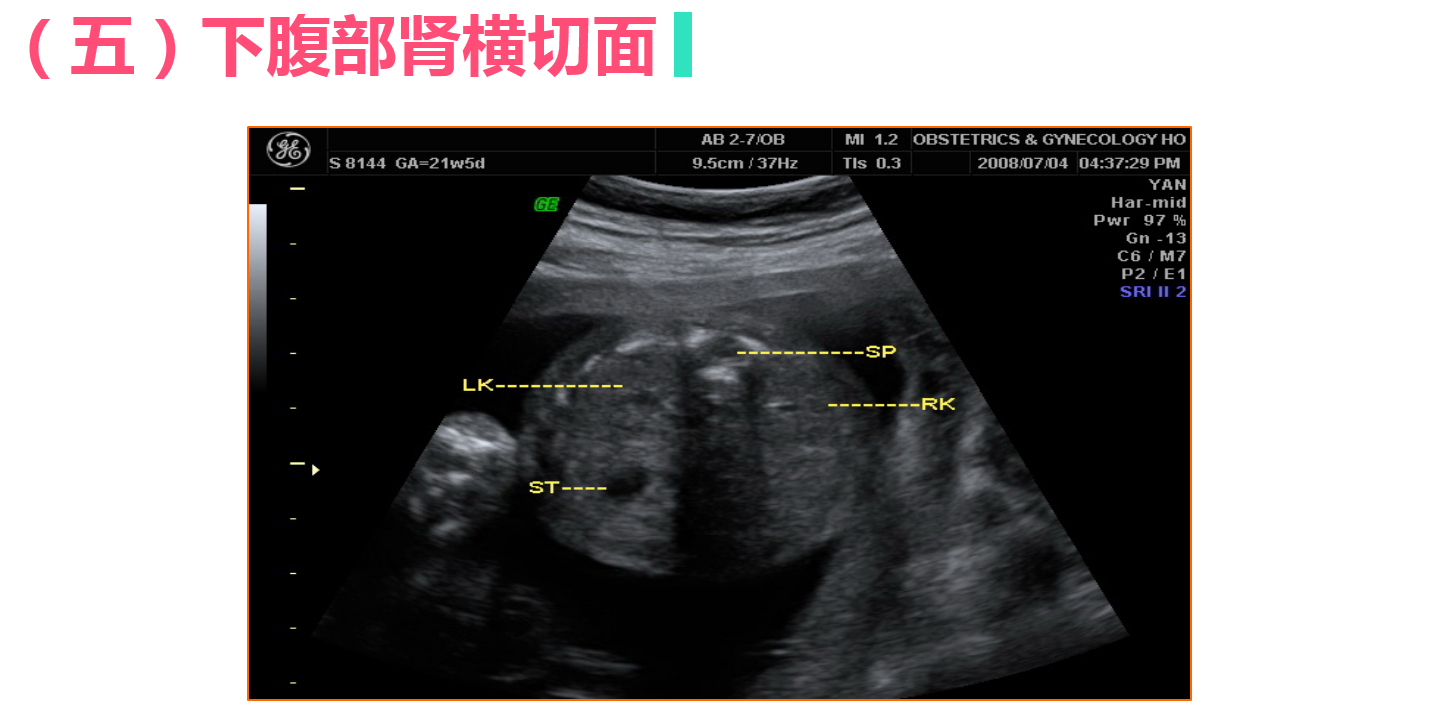

• 4.3 正常中晚期妊娠声像图

正常中晚期妊娠声像图